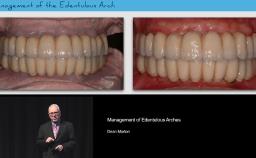

In this lecture, the second of a two-part series, German Gallucci discusses how overall treatment times can be shortened by careful selection of the appropriate loading protocol and the use of digital workflows. Using a series of clinical cases to illustrate major points, he discusses the clinical recommendations of the 2013 ITI Consensus Conference, and how digital workflows – digital planning, guided implant placement, and digital impressions – can be used to achieve optimal patient-centric outcomes in implant treatment plans. This presentation focuses mainly on full-arch fixed dental prostheses for edentulous patients; implant-supported and implant-retained overdentures are briefly discussed.